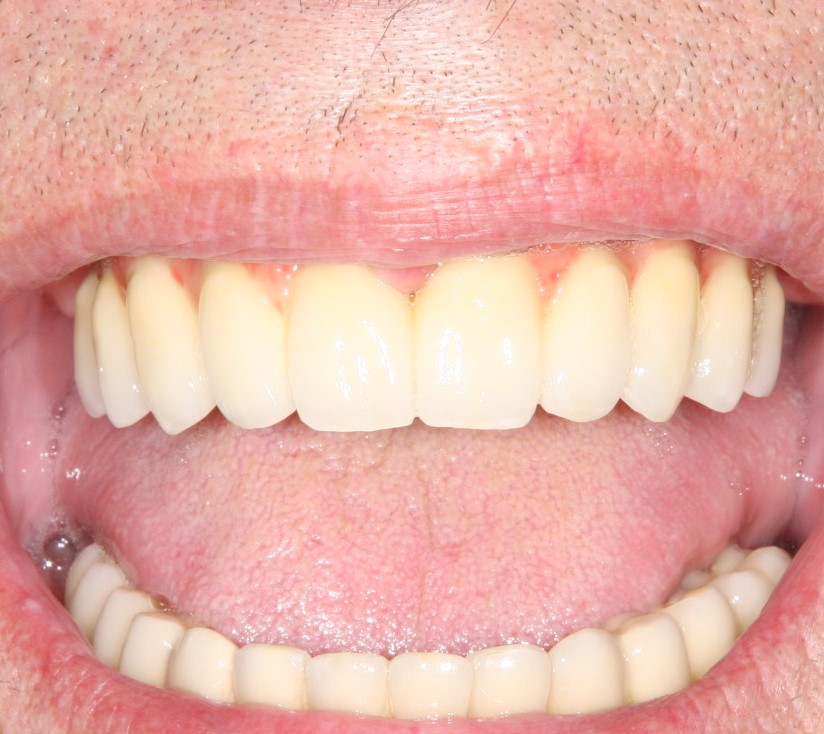

Конечно, наличие трансгингивальной части накладывает серьезные ограничения по установке трансгингивальных имплантов. В частности, их почти не используют в эстетически значимой зоне, они очень требовательны к правильному позиционированию и биотипу слизистой оболочки. Зато идеальны для фиксации условно-съемных конструкций при тотальном отсутствии зубов:

Из-за узких показаний к применению, трангингивальные импланты на рынке встречаются нечасто. Наверное, первым приходит на ум Straumann TL, XiVE TG, Zimmer Spline и т. д.

Ну и, трансгингивальные имплантаты, в определенных условиях, делают хирургическую часть имплантологического лечения проще и дешевле: